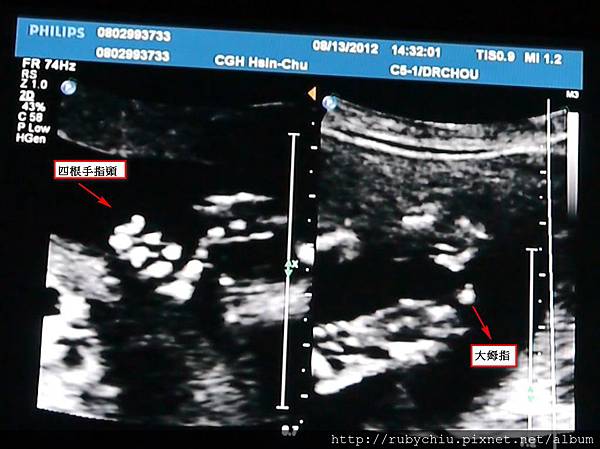

另外拍了很久的手手啦!這隻有一隻手!有四根手指,加大姆指特寫!

另外一隻手我就沒有截取圖案啦!